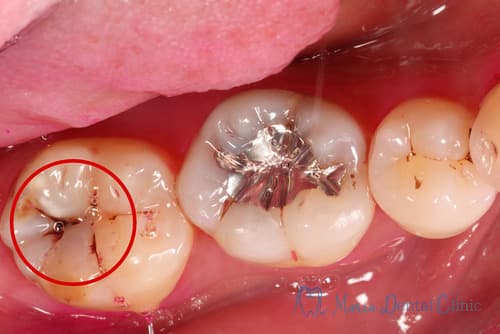

う蝕検知液染め出し後の写真、虫歯除去後の写真

虫歯を除去する際には、臨床感や手指感覚に頼らず、う蝕検知液を用いて虫歯を染色することが大切です。

そして、ライト付きのルーペやマイクロスコープなどの拡大下において、染色された虫歯を徹底的に除去し、且つ健全な歯質をできる限り保存することが重要です。

虫歯治療の写真

虫歯治療後に行う歯の詰め物には 機能回復、虫歯の再発の予防、歯の強度の維持 の意味が含まれます。基本的には機能の回復は咬合を付与できれば達成されます。しかし、虫歯治療後に再発を予防するためには、適切な処置を完璧に行う必要があります。